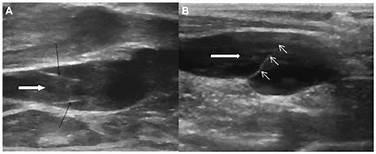

Image of Valves

Veins have the lowest pressure and need valves to ensure blood flows in the correct direction in the vessel (just like lymphatic vessel). As you can see from the graph, blood pressure and velocity drop rapidly as it enters the capillaries because the total vessel volume rapidly increases.This provides maximum time for exchange of materials between vessels and cells.